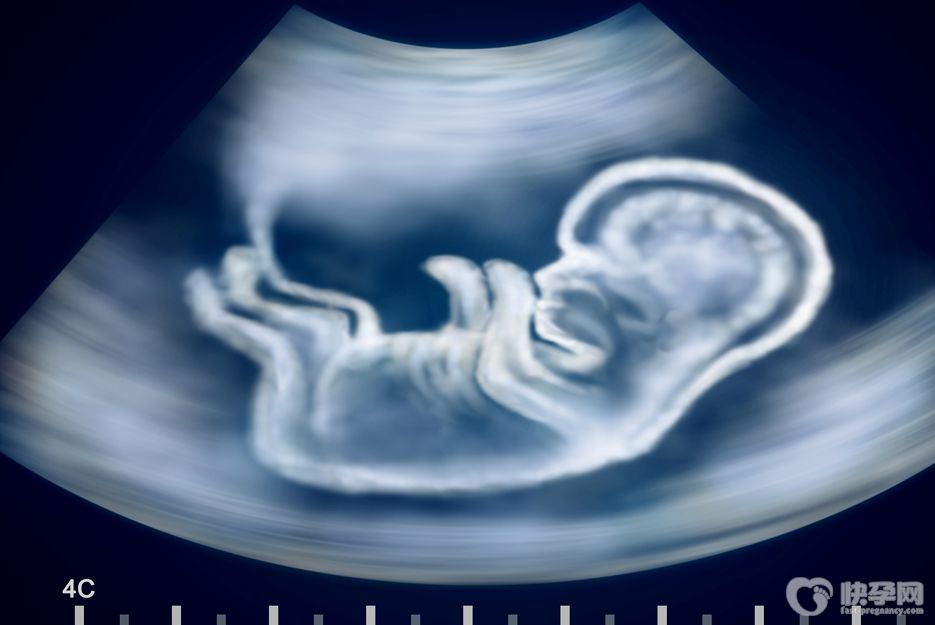

都知道试管技术是不孕不育夫妻的救星,但试管也不是你想做就能做的,做试管婴儿需要满足的五大条件缺一不可: